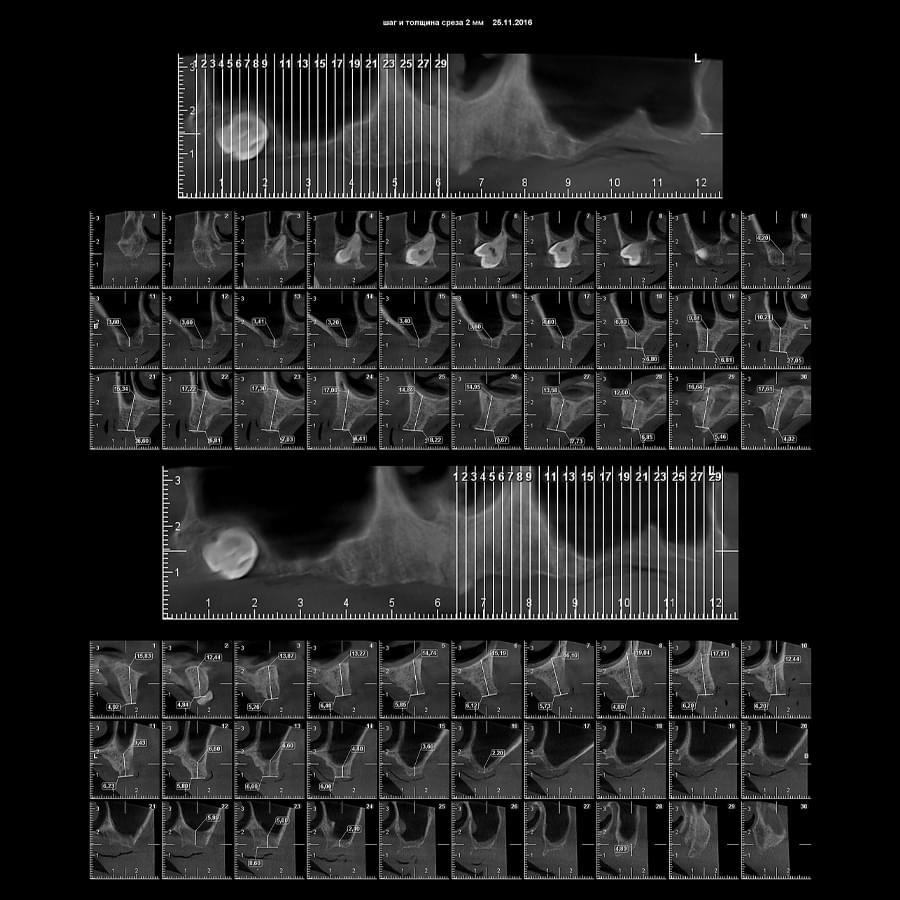

Отримайте вичерпну інформацію про стан ЛОР-органів завдяки надточній діагностиці на апараті

PLANMECA. Наші знімки дозволяють детально візуалізувати всі групи навколоносових синусів,

структури остіомеатального комплексу та анатомію носової перегородки.

Ми надаємо не просто знімок, а повний діагностичний сервіс:

Детальний опис: Кожне дослідження супроводжується професійним висновком лікаря-рентгенолога

з описом виявлених патологій (кісти, поліпи, сторонні тіла, рівень рідини, потовщення

слизової).

Зручна візуалізація: Можливість перегляду структур у будь-якій проекції (аксіальній,

корональній, сагітальній) для точної локалізації запального процесу.

Весь архів досліджень ваших пацієнтів надійно зберігається на вашому персональному хмарному

диску на нашому сервері — доступно в один клік у будь-який момент.